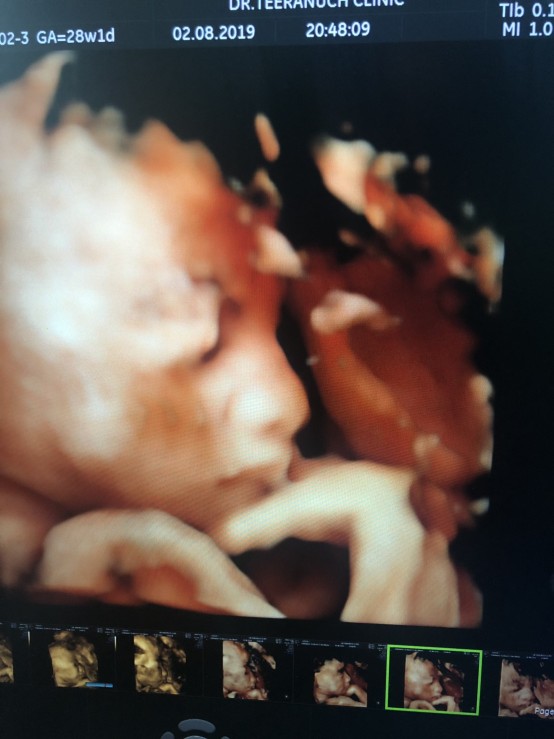

ตอน28w